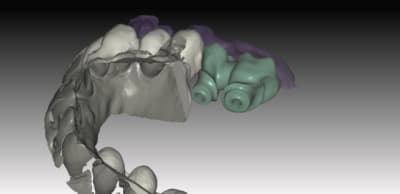

le ptit dernier pour la route

IMPLANT NB REPLACE

nouveauté du system . 2 ccZR transvissées SOLIDARISEE sans base titan

sur des connections interne....

J insiste sur la possibilité et l'avantage de régler les profils d'émergences . de un, on epouse parfaitement la gencive sans trop la mal traiter , et de 2 l'aspect final des couronnes s'en ressent car on a beaucoup moins cet effet de cintrage au collet de la dent qui souvent donne des etrangetées morphologique .

Vous pouvez voir également le puit ( en occlusal)qui depasse de la structure et qui epouse la morpholgie de la ceramique à venir .. assez sympa et bien pratique pour vous lors du rebouchage avec le compo ...